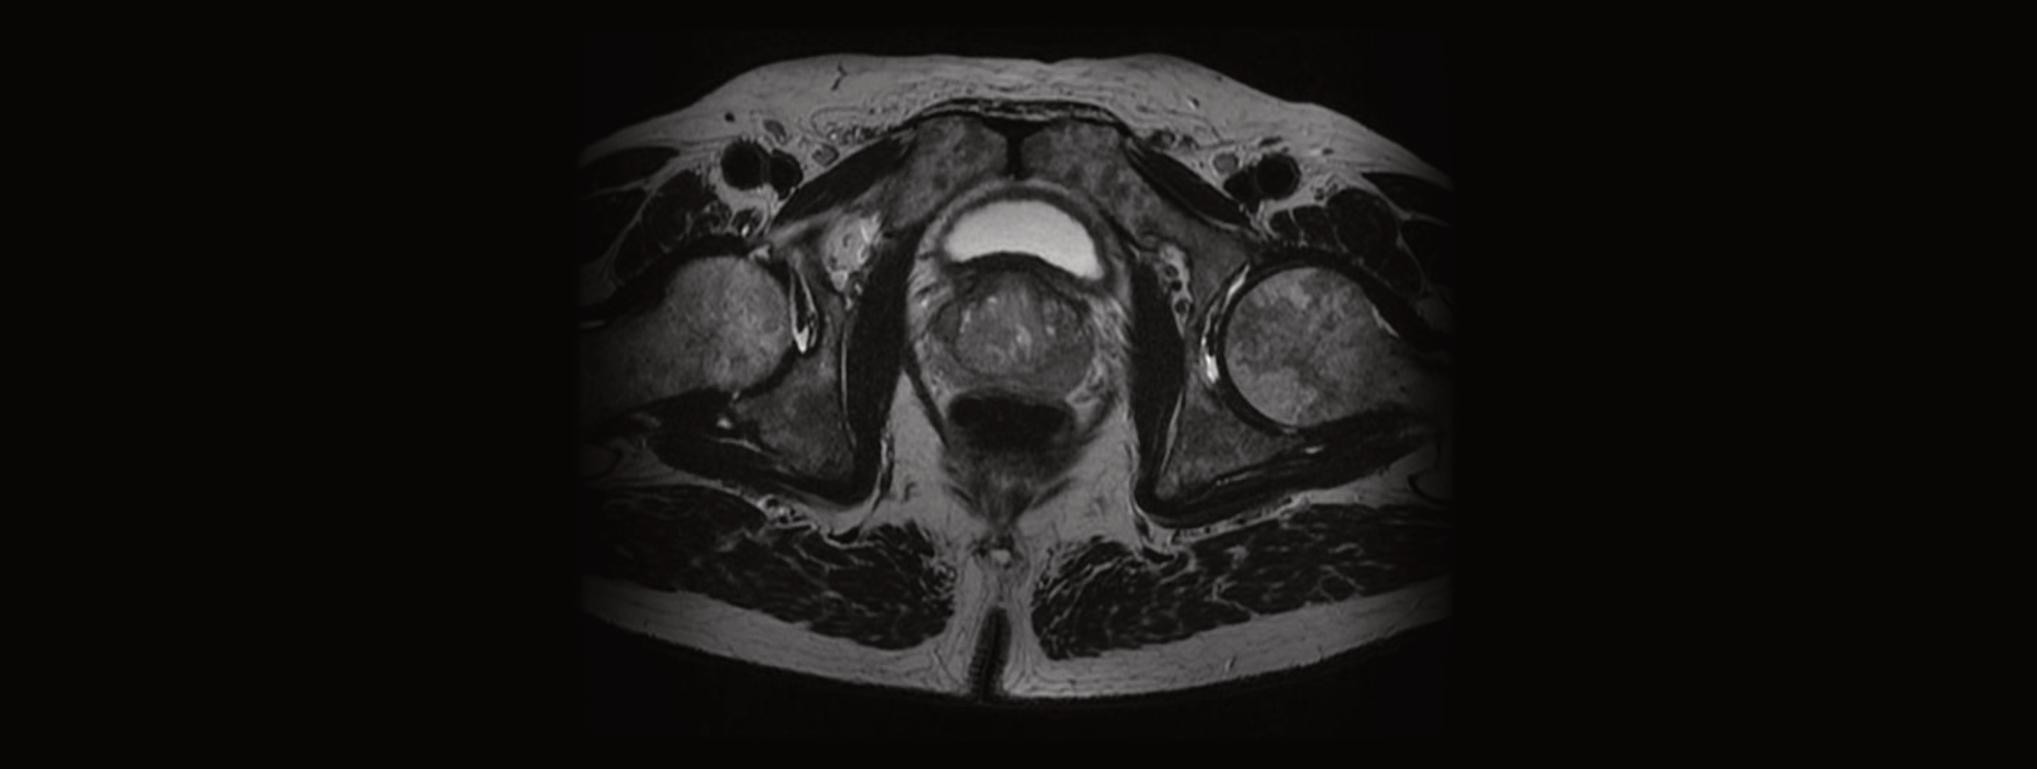

ImágenesporResonanciaMagnética(IRM) transrectal. Procedimientoparaelqueseusan unimán,ondasderadioyunacomputadoraa findecrearunaseriedeimágenesdetalladas deáreasdelinteriordelcuerpo.Seintroduce porelrectountransductorqueemiteondasde radiocercadelapróstata.Estoayudaaquela máquinadeIRMtomeimágenesmásclaras delapróstatayeltejidocircundante.LaIRM transrectalserealizaparadeterminarsiel cáncersediseminófueradelapróstata,alos tejidoscercanos.Esteprocedimientotambién sellamaimágenesporresonanciamagnética nuclear(IRMN).AvecestambiénseusalaIRM transrectalduranteunabiopsia.Enesecaso sellamabiopsiaguiadaporIRMtransrectal.

Superior:dosimetríadeirradiaciónprostática conplanificaciónconvencional3D.